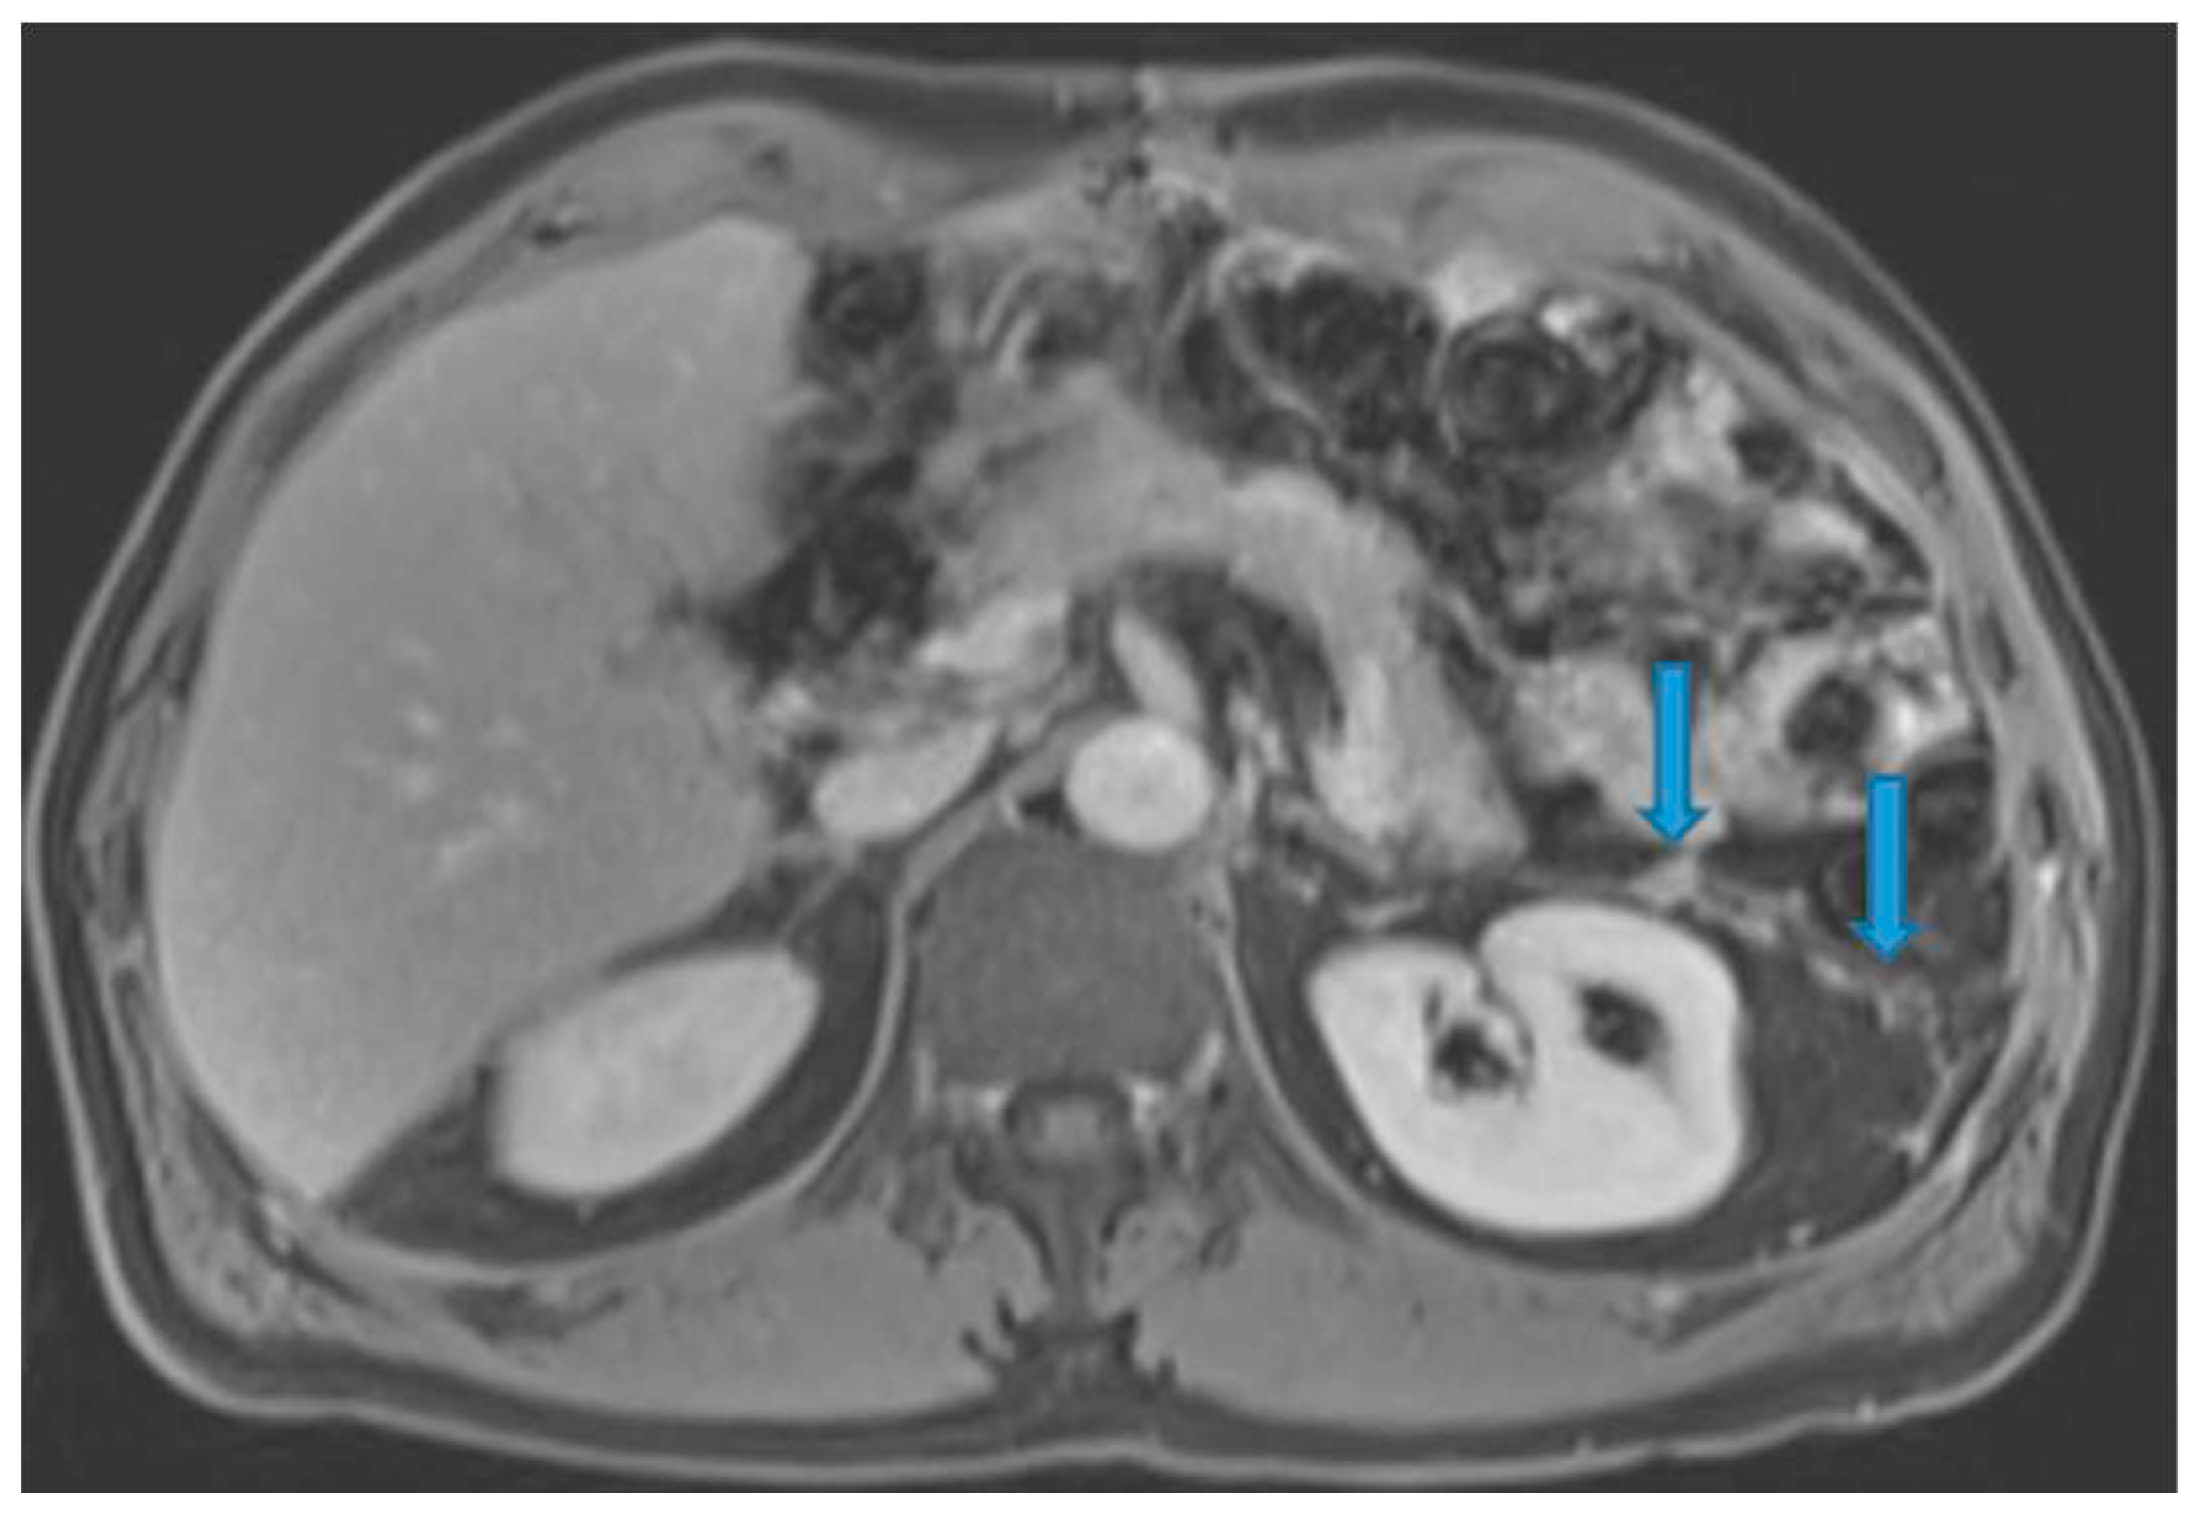

Figure 26.

Axial CE-CT (A). PC from stomach adenocarcinoma: Stellate mesentery. Axial CE portal phase FST1WI (B). PC from lobular breast adenocarcinoma: Stellate mesentery, notice the perivascular distribution. Axial CE-CT (C), axial T2WI (D). PC from stomach adenocarcinoma: Isolated perivascular deposit within the mesentery, as a soft tissue mass surrounding a branch of the SMV.